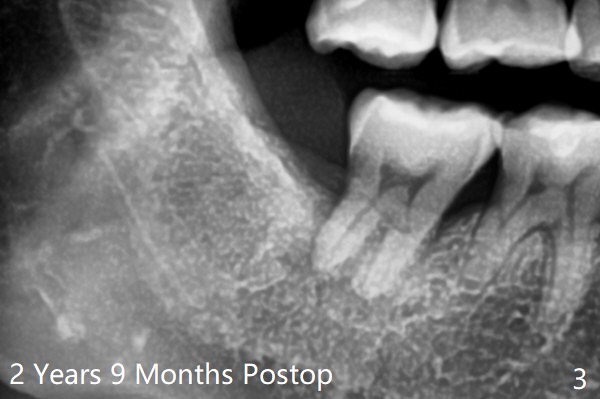

There is bone regeneration at #32 socket 2 years 9 months postop (Fig.3).